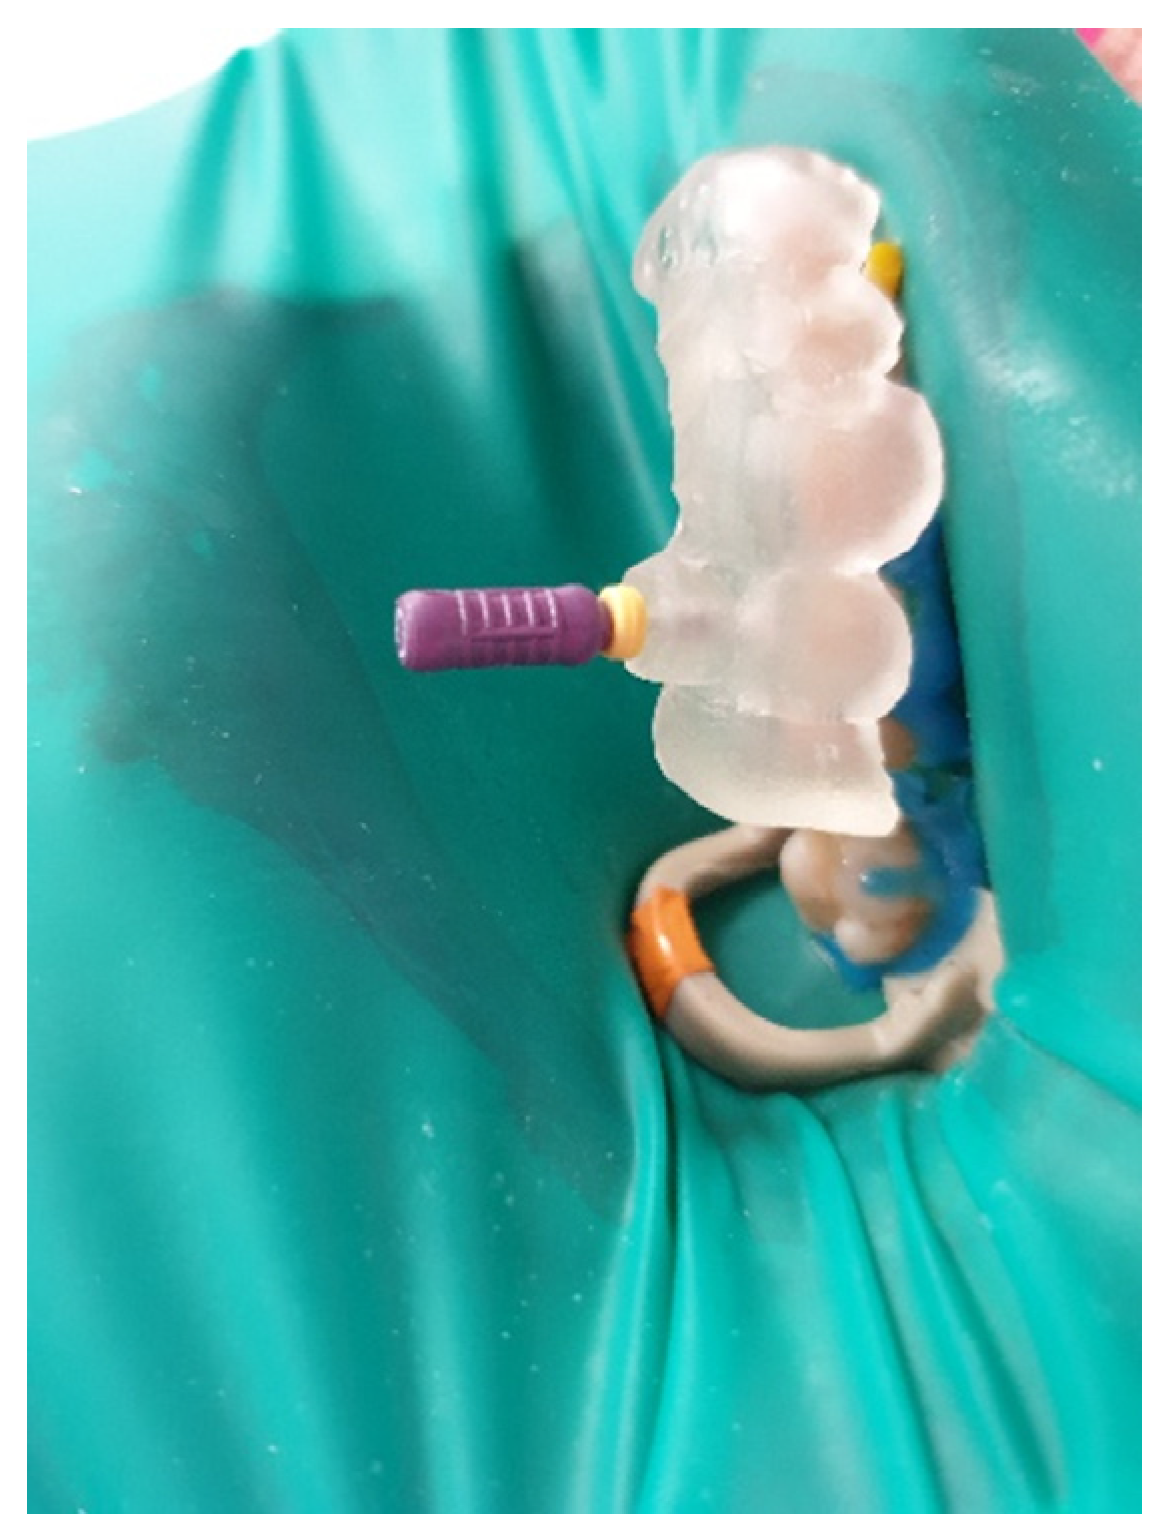

| Control the fit of the guide before and after placing rubber dam |

| Make a sign through the guide to indicate the access point in non-treated teeth |

| Remove the enamel until dentine is exposed |

| Place the guide on the teeth |

| Work through the guide: Use rotate burs in dentine, scout the canal through the guide |

| Remove the guide to rinse the cavity and clean the burs, control endodontic access using an optical microscope |

| Perform a radiographic examination to confirm correct canal access |

| Complete the root canal treatment |